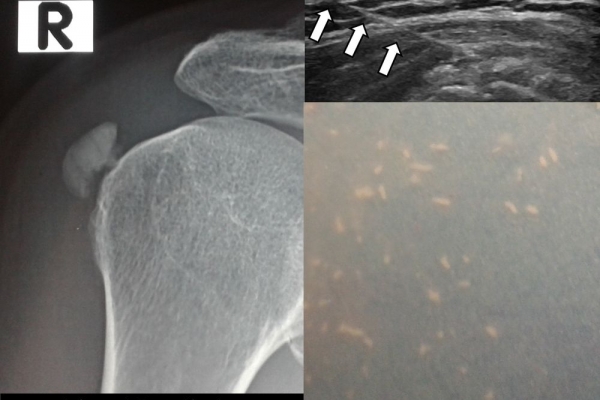

Η ασβεστοποιός τενοντοπάθεια-τενοντίτιδα είναι η εναπόθεση αλάτων ασβεστίου μέσα στους τένοντες,πιο συχνά του στροφικού πετάλου του ώμου, με αποτέλεσμα την τοπική φλεγμονή και πιθανή ρήξη του τένοντα.

Η υπερηχογραφικά καθοδηγούμενη αφαίρεση των επασβεστώσεων (barbotage) είναι μια ελάχιστα παρεμβατική (minimally invasive) τεχνική θεραπείας για την ασβεστοποιό τενοντοπάθεια. Με τους υπερήχους είναι δυνατός ο εντοπισμός των ασβεστώσεων και η διαδερμική τοποθέτηση μιας βελόνας στο κέντρο της συμπτωματικής ασβέστωσης. Στη συνέχεια γίνεται διαδερμικός τρυπανισμός και επαναλαμβανόμενες πλύσεις του ασβεστίου, με αποτέλεσμα τόσο την αφαίρεση της παθολογικής επασβέστωσης όσο και την αυξηση τοπικά της αιμάτωσης με αποτελεσμα την σταδιακή απομάκρυνση των παραγόντων φλεγμονής-ερεθισμού.